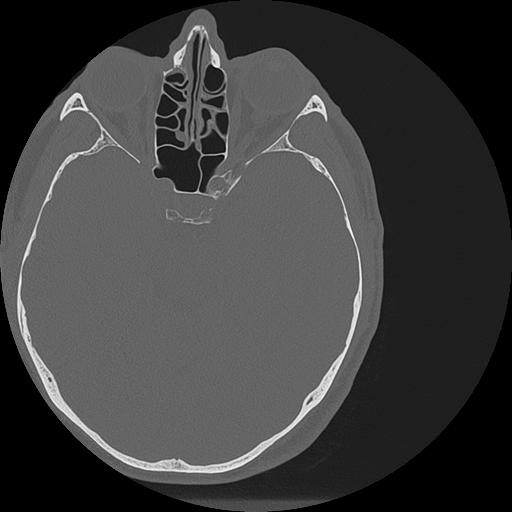

7 HUESO,,Vol,0.5,HUESO,,